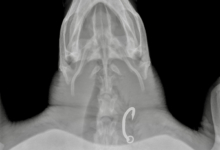

Dhontha is in overall good body condition and her blood work is acceptable, but her X-rays showed something alarming: She has a large hook lodged in her oesophaghus that will require surgical removal.